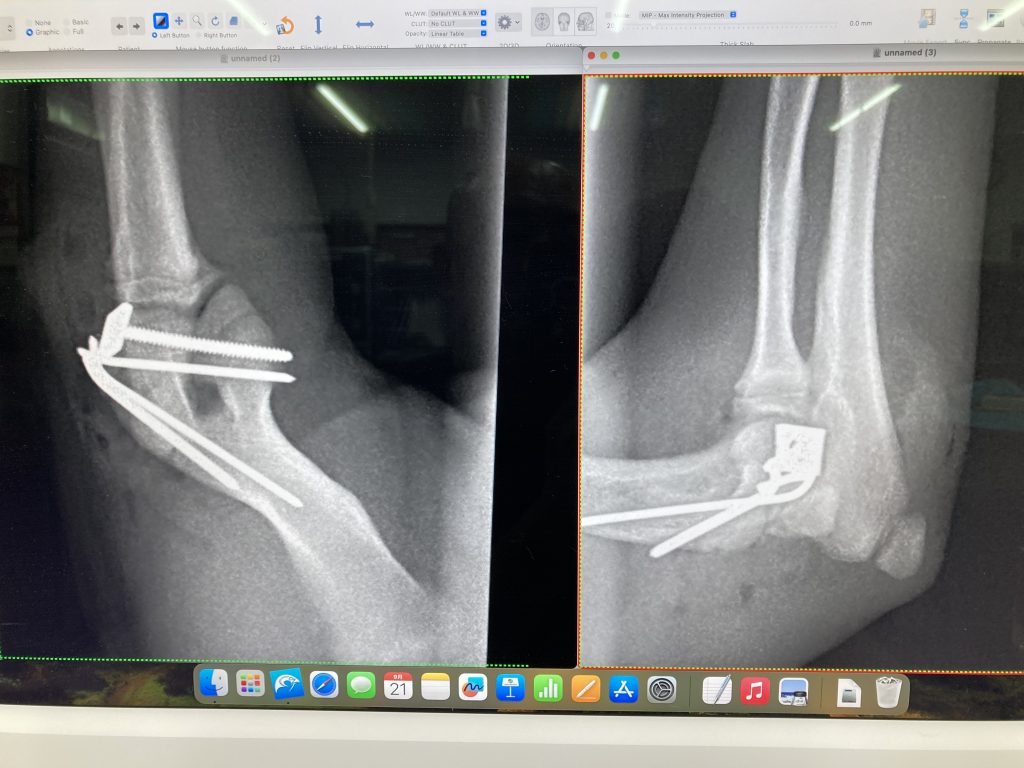

あの指はオーナーの決断によって手術となりました

腫瘍を疑い手術ですので、術前にCT検査です

暫定診断:爪の腫瘍

レントゲン検査では爪の骨が溶解していました

高齢ですが手術をお勧めしました

決断はオーナーにゆだねられます

①脾臓の腫大

②左右に大きな腎臓に嚢胞

③胆石あり

高齢です

色々見つかりました

①は転移の可能性もあるので手術時に脾臓の細胞検査

②腎不全になりやすいので点滴をしっかり

③今後の要注意

やはり高齢は一筋縄ではいきません